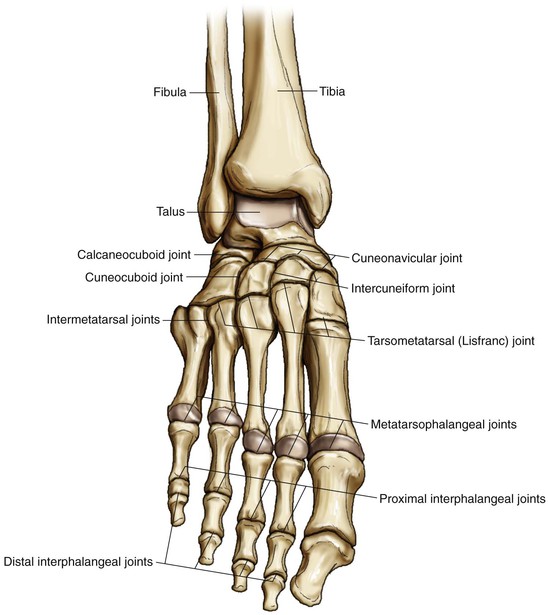

Анатомия суставов Шапарова и Лисфранка: фото и информация

Раздел: Мудрость в деталях